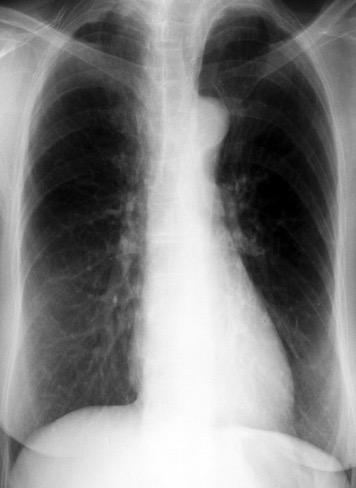

Parálisis frénica transitoria tras cirugía de válvula aórtica

Parálisis frénica transitoria post cirugía cardiaca (10%).

Puede acompañarse de atelectasia del LII.

Benjamin JJ et al. . Left lower lobe atelectasis and consolidation following cardiac surgery: the effect of topical cooling on the phrenic nerve. Radiology 1982